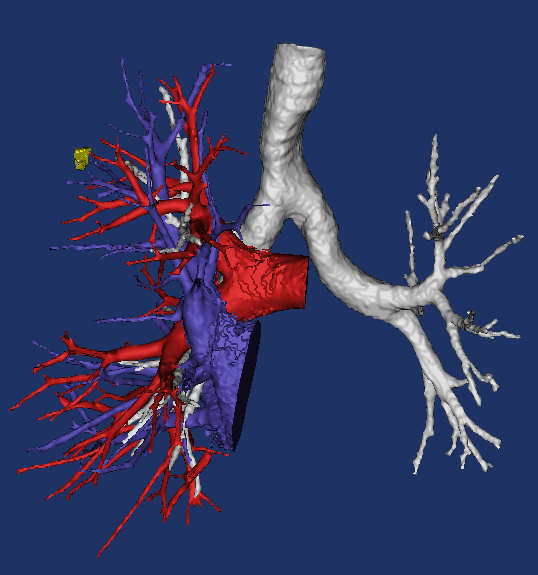

人工智能CT三维重建下精准肺段切除

随着影像及人工智能技术的发展,已有国内少数医院通过将CT图像数据导入计算机工作站,建立起三维立体模型,真实地还原了患者的动脉、静脉、支气管的走形形态,在电脑中既可以旋转观察,也可以做成三维立体动画,在手术中可以通过查看电脑中的图像导航,帮助手术准确定位并精准切除,避免出错。 三维重建优势在于:1.清晰的三维图像使手术医生较轻松地识别解剖结构并有效降低手术医生辨别解剖结构的难度;2.术前充分了解解剖的变异,避免周围重要结构的损伤,为术前个体化手术方案的制定提供重要依据;3.模拟手术范围,判断手术切缘,确定合理的肺段切除方案;

减少对结构的不必要的探查,减少创伤,缩短手术时间,有可能减少并发症的发生率;4.帮助年轻医师熟悉解剖结构,缩短学习曲线。5.肺段手术规划目标:三维影像导航技术:如同汽车导航,提前规划,避免绕弯路,安全快速到达。

CT三维重建立体影像